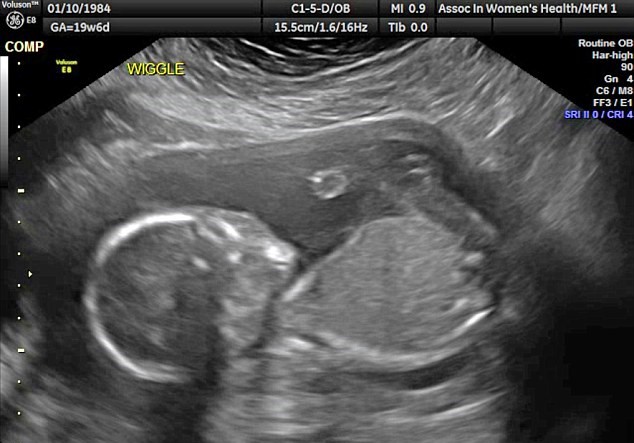

WICHITA – YOUTUBE Feto si prende a cazzotti in testa. Una coppia che vive a Wichita in Kansas è rimasta sorpresa nel vedere il feto del loro primo figlio che si prende a cazzotti in faccia. Almeno questo è quello che si vede nell’ecografia 3D pubblicata sul Daily Mail: il bambino appare molto irrequieto e sembra colpirsi con dei pugni sulla testa. Dave e Vanessa Watson sono rimasti di stucco nel vedere Edward James, questo il nome scelto per il pargolo, che si dà i pugni sul viso.

L’ecografia in questione è quella delle 20 settimane e risale allo scorso 26 gennaio. Vanessa, 32 anni , e Dave, 37, sono sposati da due anni e sono in attesa del loro primo figlio. Parlando della radiografia, Dave, un gestore di servizi per la ristorazione racconta: “E’ stato un vero choc. Stavamo guardando l’ecografia in tempo reale e improvvisamente è accaduto questo. L’infermiera si è messa a ridere e ci ha detto che non aveva mai visto niente del genere”.

A 20 settimane di età il feto misura, in genere, circa 26 centimetri. Il feto è già in grado di girarsi e di eseguire capriole.